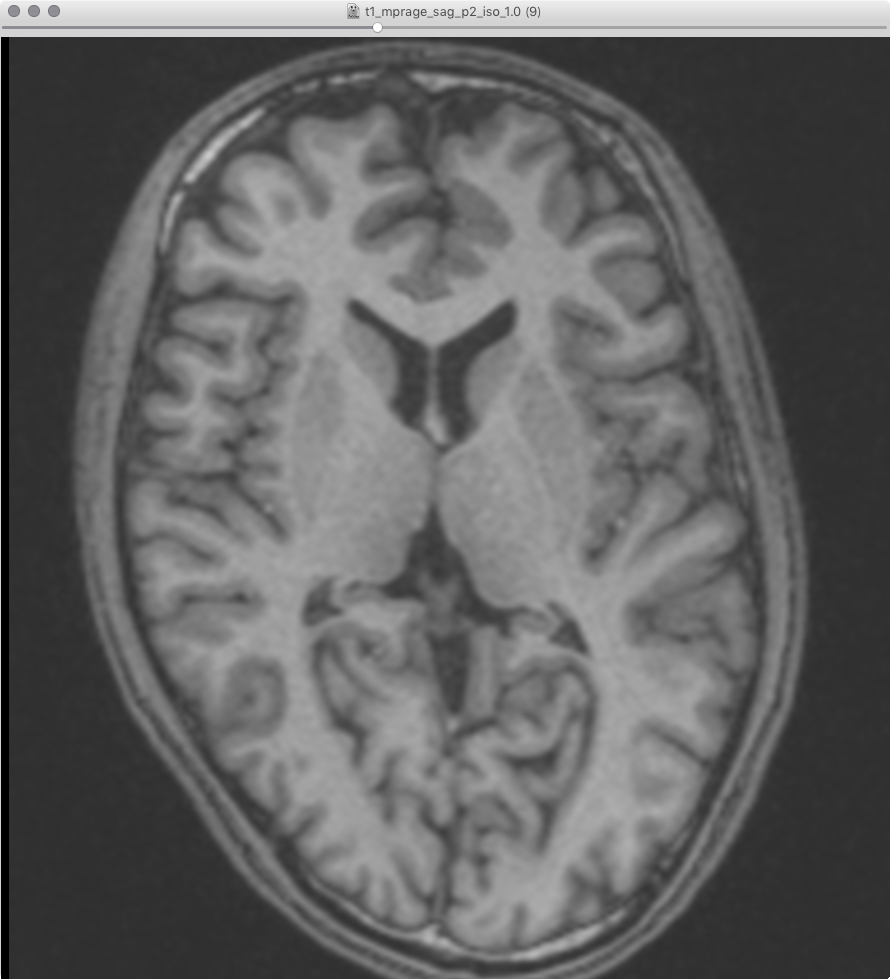

画像サンプル |

---|